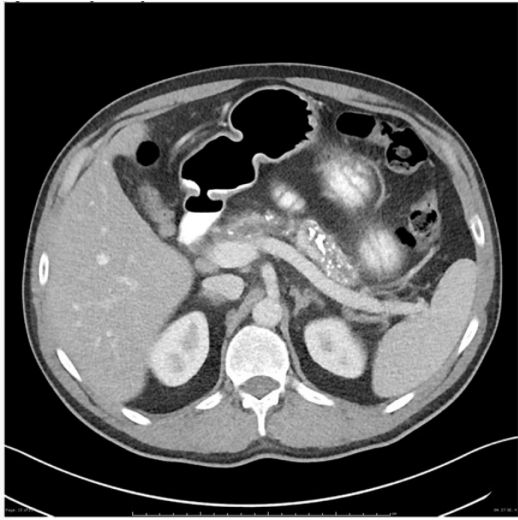

MSL, 55 anos, comparece ao hospital com quadro de dor abdominal, inespecífica, com piora após as alimentações, iniciada há cerca de

10 dias. Refere ser alcoolista crônico; porém, nega qualquer outra comorbidade. Realizada tomografia computadorizada de abdome,

como atesta a figura abaixo:

Figura 1 –Tomografia computadorizada de abdome.

Qual seria a hipótese diagnóstica compatível com o caso apresentado e os achados de imagem que podem estar associados, além dos que são apresentados no exame?